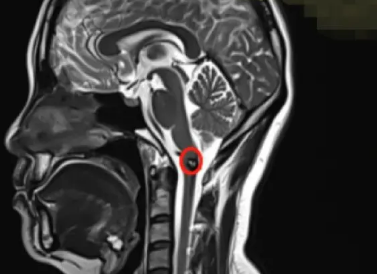

疾病最初在2017年首次出血时发现。当时患者加班较多,某个下午突然出现身体一侧麻木症状。这种麻木感不同于姿势压迫所致,涉及头部、面部、手臂及手指,伴随无力、进食困难及耳闷感。次日进行脑部MRI检查,发现脑干存在畸形血管团,确诊为延髓海绵状血管瘤。